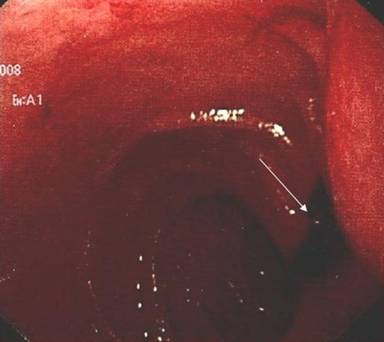

One day after admission, the occurrence of hematemesis urged repeated endoscopy, which revealed the fresh blood originating from the papilla of Vater (Figure 1). Endoscopic retrograde cholangiopancreatography was performed, demonstrating patent pancreatic duct and blind remnant of native common bile duct without communications between pancreaticobiliary tract and blood vessels. During the procedure few blood clots originated from the papilla of Vater. Multislice contrast computed tomography showed moderate enlargement of the pancreatic head with suspected hematoma (Figure 2), along with three splenic artery aneurysms, of 30 mm, 12 mm and 8 mm in diameter, in the distal arterial segment, as well as anastomotic stenosis of native and donor hepatic artery. However, contrast extravasation on visceral angiography was not detected (Figure 3). The embolization of the splenic artery aneurysms was judged unfeasible due to tortuosity of the splenic artery, wide neck of the major aneurysm and proximity of other two aneurysms to the splenic hilum. Supportive therapy stabilized the patient and gastrointestinal bleeding resolved. The patient was scheduled for surgery; however, subsequent development of hepatic artery thrombosis, resulted in multiple liver abscesses and septic episodes (Figure 4). On several occasions Enterococcus faecium and Klebsiella pneumoniae were identified from abscesses and blood cultures. Despite of a broad-spectrum antibiotic therapy and percutaneous drainage the fever persisted, although gastrointestinal bleeding did not reoccur. Three months later, the patient underwent liver re-transplantation and splenectomy. During the three past years of follow-up, the patient has remained uneventful.

Figure 1. Upper endoscopy showing fresh blood originating from papilla of Vater (arrow). |